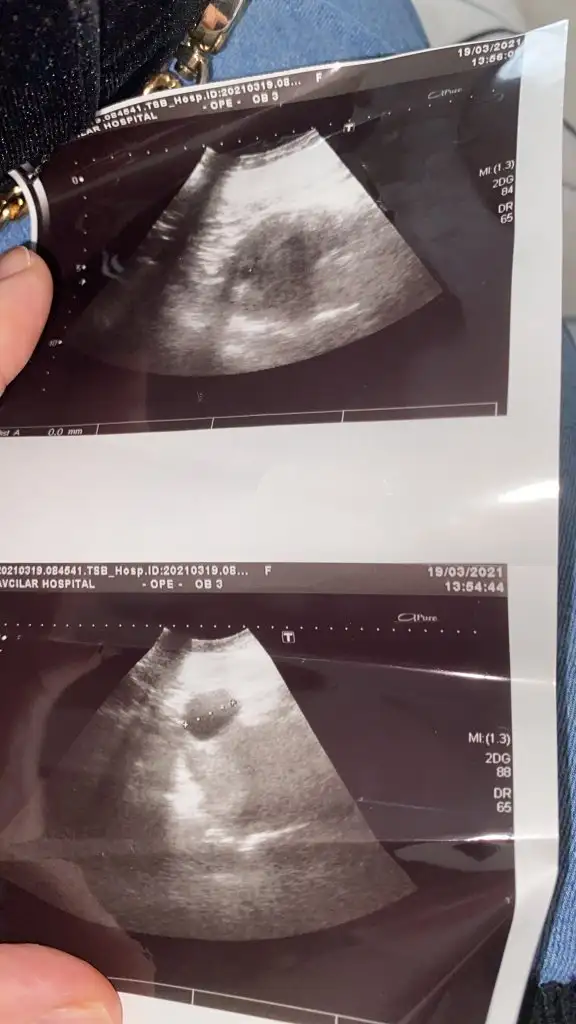

Banada bakabilirmisin lutfen vajinal ult. 9hafta

Eklentiler

• 8666_20210318-115037_7.webp

22,6 KB · Görüntüleme: 70

• 8666_20210318-114945_5.webp

23,2 KB · Görüntüleme: 75